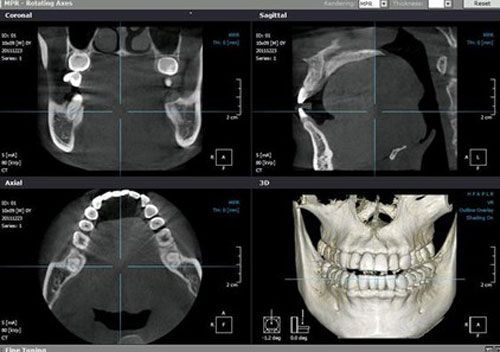

We are equipped with the PointNix 3D digital radiology system, with large scale, high-resolution image capture. Through this equipment we can perform a highly detailed, 3-dimensional analysis of the structure of the teeth, bones and neighbouring tissues. The digital image is delivered together with all the other computerised digital studies for that patient

3D radiology analysis programs such as SimPlant® or RealScan, place the complete radiographic profile in our hands.

We can, for example, determine the ideal position for the placement of dental implants, calculate bone density and quality, reach a prognosis for the treatment, manufacture templates, surgical guides, perform virtual surgery, 3D virtual endoscopy, etc.

They provide much more information than conventional X-rays and also use a minimal amount of radiation.